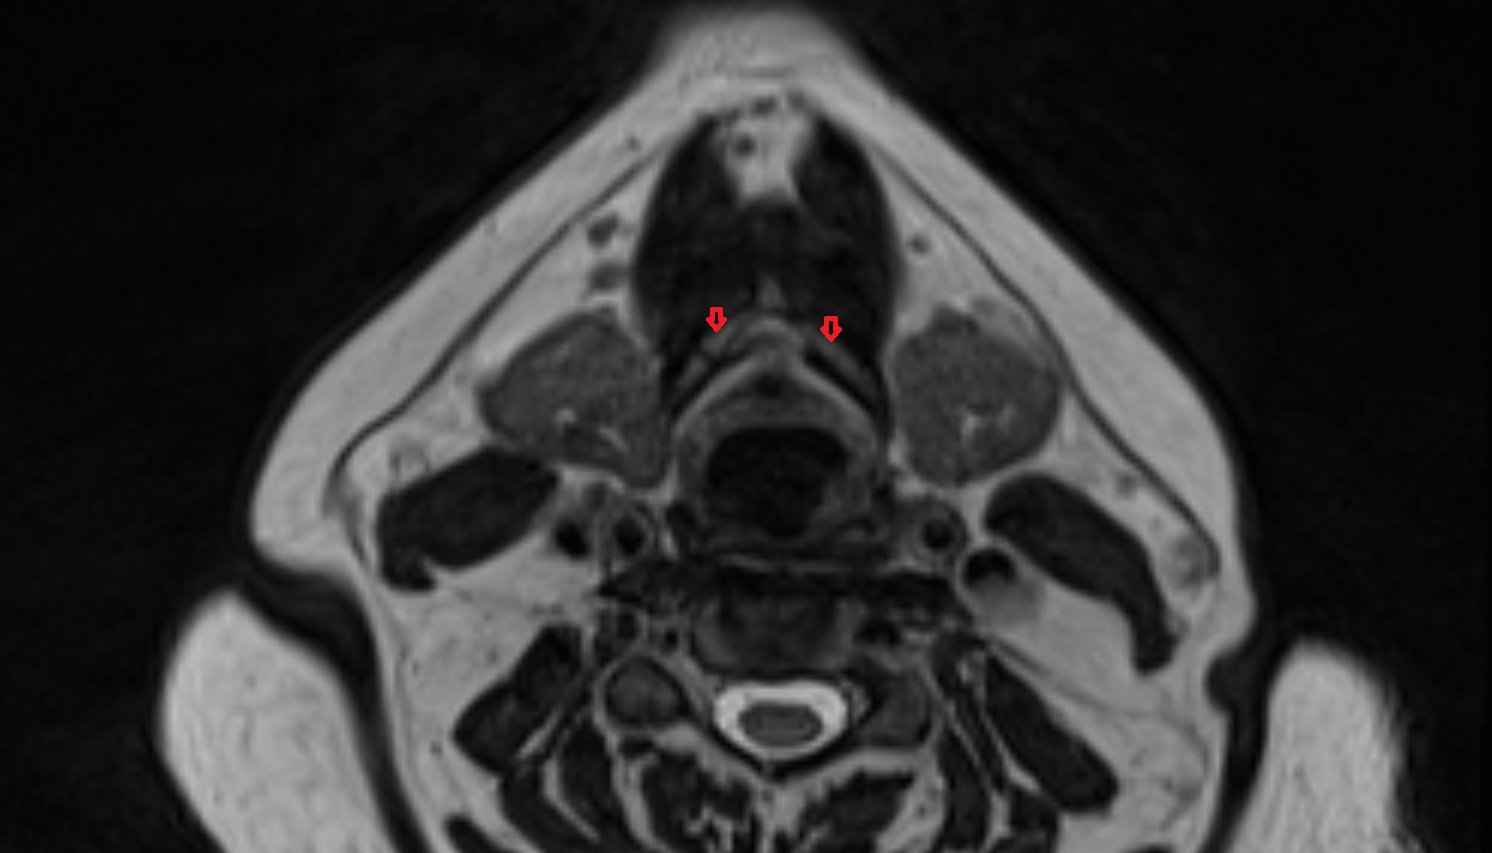

- Temporomandibular joint